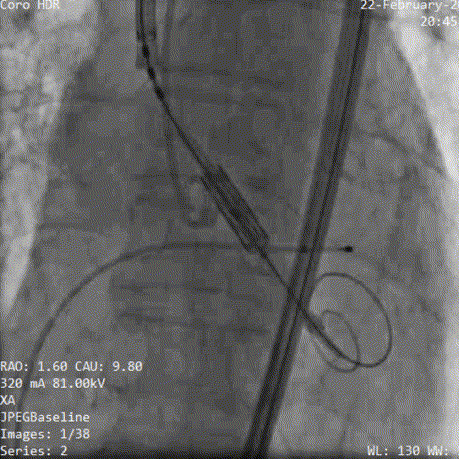

术中影像:

3.精细调节位置,改变投照角度,获取瓣架切线位定位

4.展开瓣膜